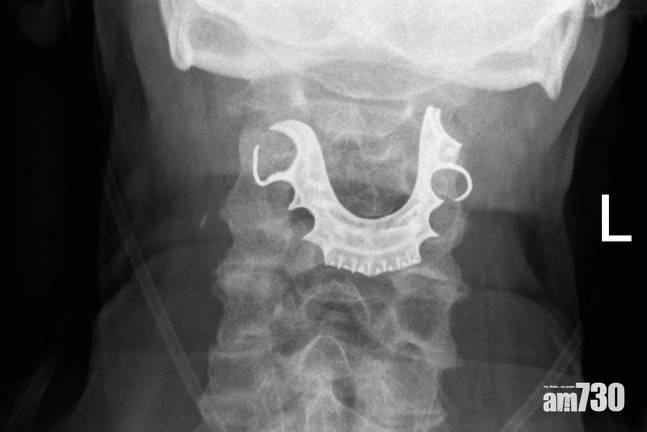

香港防癆會中醫診所暨香港大學中醫臨床教研中心註冊中醫師何肇婷表示,「梅核氣」患者猶如「痰上頸」,一般不會影響吞嚥或進食,常要「清喉嚨」,其臨床經驗幾乎每周都接獲一至兩宗類似的求診個案。一般問診後,患者均沒有咳嗽、流涕等外感症狀。她指出,男女均有機會出現「梅核氣」,患者的年齡層很廣,但以中青年及更年期女性為多,主因與情志不暢,引致肝氣鬱結或肝氣犯脾,影響津液運化,凝結成痰並結於咽喉,而且不時復發。

醫師一般會先檢查咽喉,以排除其他咽喉疾病,何肇婷表示,梅核氣患者除咽內有異物感的典型症狀外,或有精神抑鬱、心煩、胸脅脹滿、胃納不佳或消瘦等症狀,婦女亦常見月經不暢。她引述一名年約55歲的女患者,常感到喉嚨有痰,每日起床或夜晚上床前情況更為嚴重,甚至試過因「清喉嚨」而咳傷喉嚨,問診後發現患者是家庭主婦,本身性格較為急燥,容易緊張,故屬典型的「梅核氣」症狀,之後建議一些疏肝解鬱的方法及多做運動,情況便得以改善。